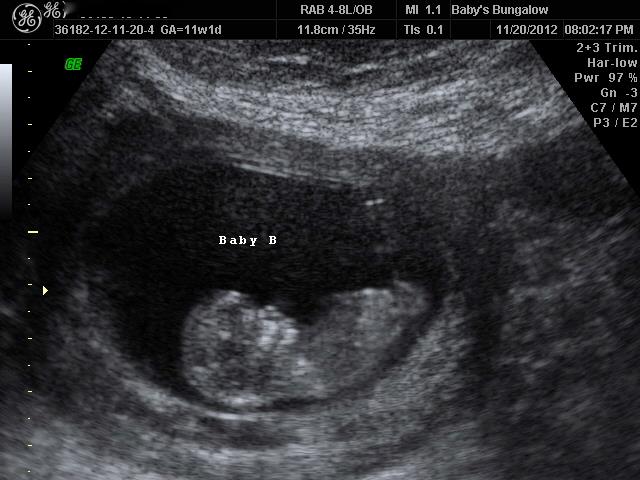

Anyway, the tech was great and got lots of good shots of the babies, even some in 3D, which we weren't expecting. Then the owner of the place came in, and they both were examining the shots and talking to each other about how it seems like they could give a good guess on the babies' genders. They said it would be just a guess, as it was so early, but they were pretty sure that Baby A was a girl, and that Baby B was a boy. In fact, they said they'd be shocked if Baby B was anything but a boy - they said he had a very clear boy nub.

I was totally okay with thinking I'd get one of each, even though I'd love two girls. But then things took a turn for the worse, and suddenly, they weren't sure about Baby A being a girl anymore. They said the nub looked flat in some shots, then slightly angled in others. They looked and looked, and then finally decided that they really couldn't tell with Baby A, but were pretty sure Baby B was a boy.

Baby B

Attachment 6510

What do you think? Can you even see any nubs in these pictures? It was a lot clearer during the ultrasound session, maybe I should have bought the CD. I have another question too - once a nub is rising, or if it's "slightly raised," there's no chance of it going down, right? I mean, at this stage, all nubs are pretty flat, and then rise if they're boys, right? I admit I'm not great at the nub theory, and I do realize it's very, very early to even be obsessing about this....but I feel like all my hope for ever having a girl has just been totally squashed.